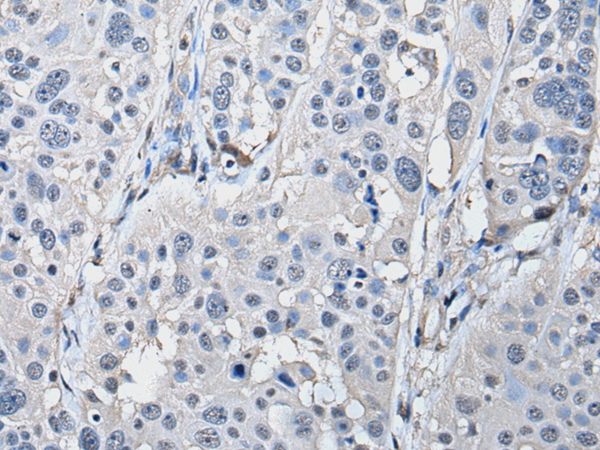

分类: 科研抗体货号: P01677别名: RMD3; RMD-3; FAM82C; FAM82A2; ptpip51应用: WB,IHC反应种属: Human, Mouse, Rat